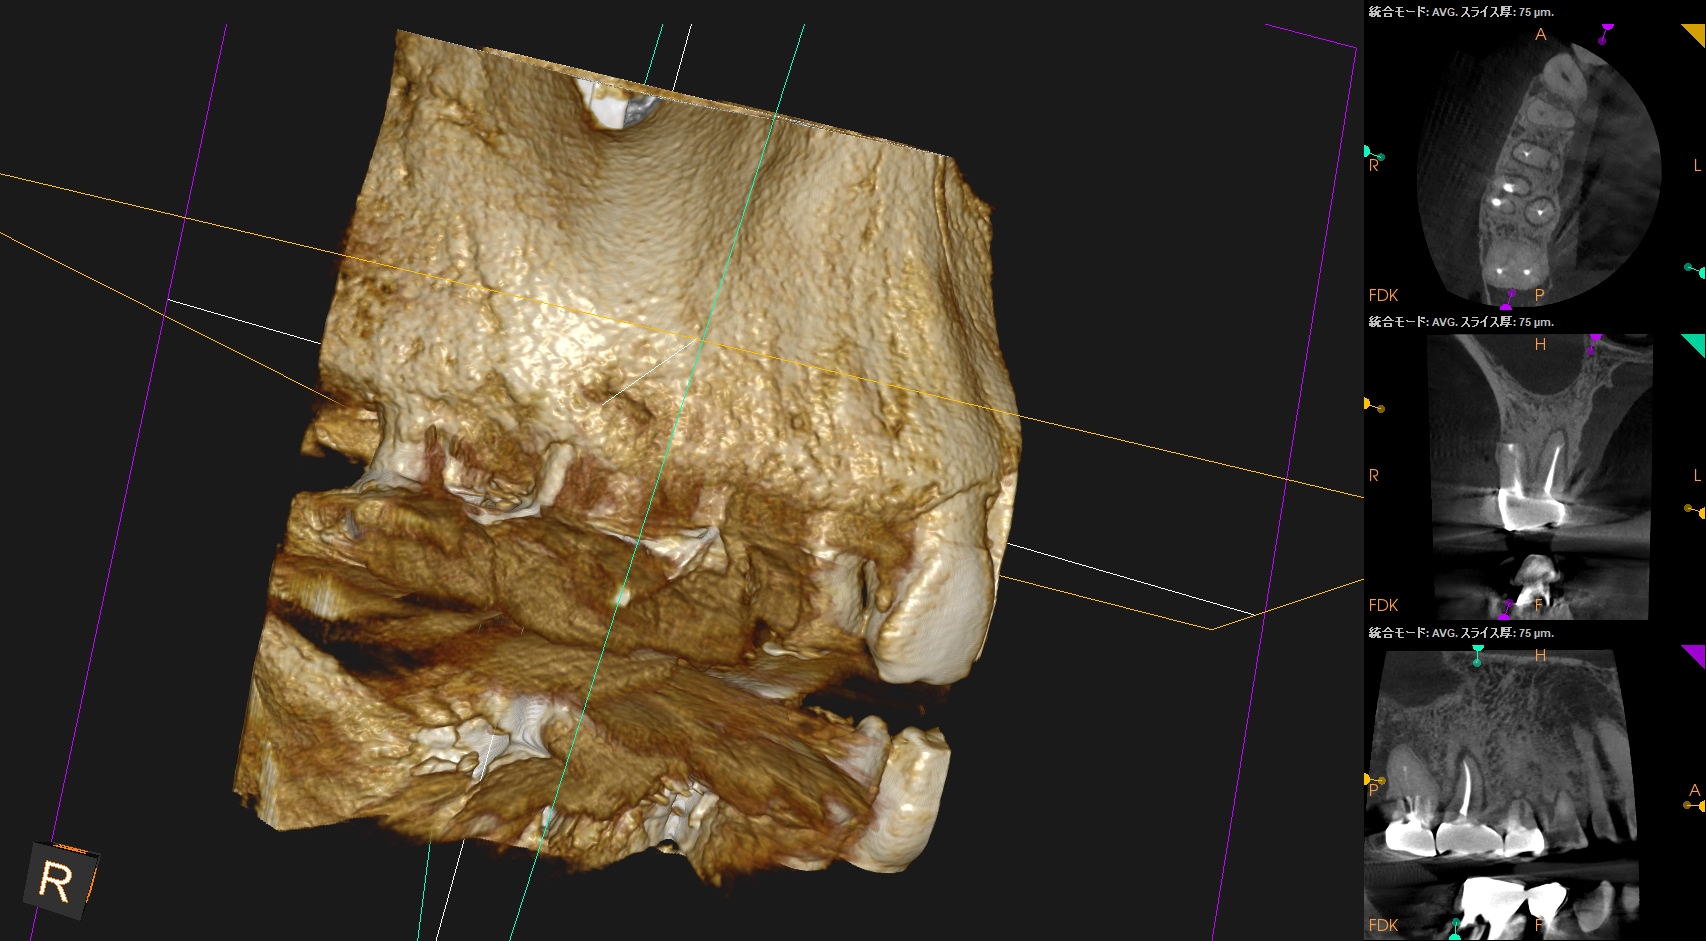

Pre-op CBCT(2024.11.25)

MB

DB

P

B

P根以外のMB,DBには根尖病変がありSinus tractがある。

ということは…

MB+DB Apicoectomyだ。